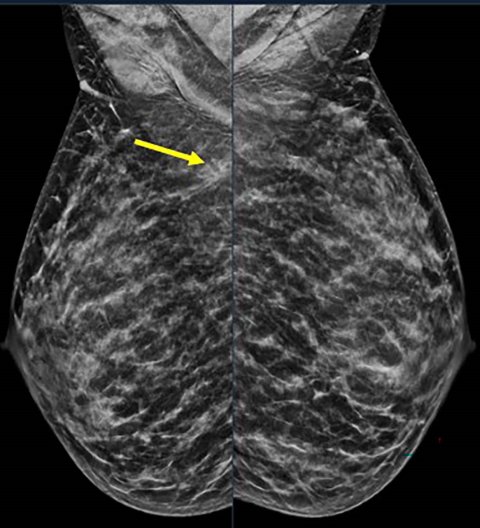

Image credit: Stamatia Destounis, M.D., and RSNA

A total of 1,799 breast cancers were diagnosed in 1,290 women, aged 18 to 49. Annual breast cancer diagnoses in this group ranged from 145 to 196, with a mean age at diagnosis of 42.6 years (range 23-49). Of these, 731 (41%) were detected on screening and 1,068 (59%) on diagnostic evaluation. There were 1,451 invasive cancer cases (80.7%), and 347 (19.3%) non-invasive cancer cases. “Most of these cancers were invasive, meaning they could spread beyond the breast, and many were aggressive types—especially in women under 40,” Dr. Destounis said. “Some were ‘triple-negative,’ a form of breast cancer that is harder to treat because it doesn’t respond to common hormone-based therapies.”

Even though women under 50 made up 21% to 25% of the patients that were screened yearly, they consistently accounted for one out of every four breast cancers found each year. “This is striking because it shows that younger women not only carry a stable and substantial share of the breast cancer burden, but their tumors are often biologically aggressive,” she said. “That combination—steady incidence plus disproportionately aggressive biology—directly challenges age-based screening cutoffs and strengthens the case for earlier, risk-tailored screening approaches.”